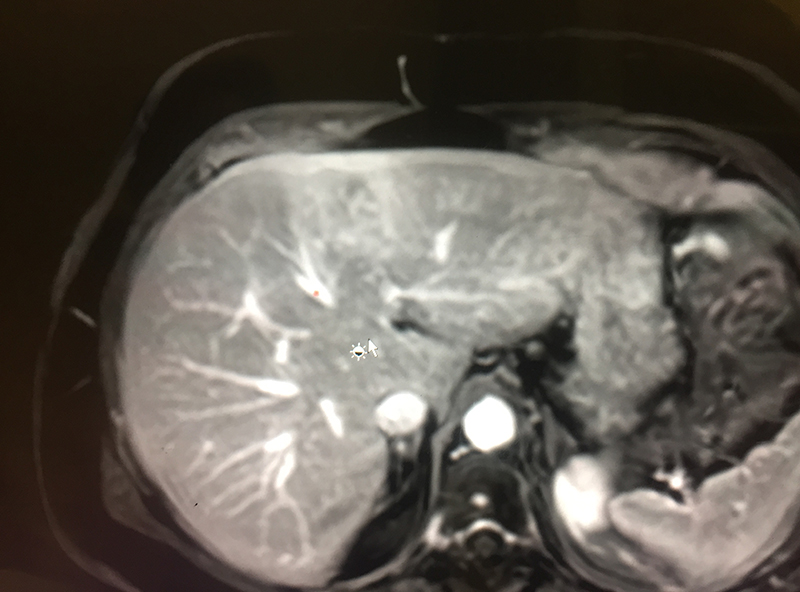

cholangiocarcinoma in the left side of liver

78 year old lady with abdominal pain was diagnosed to have liver cancer (cholangiocarcinoma) in the left side of liver. The tumor was in a curative condition and she was fit to undergo the major surgery (left liver resection). She underwent a left hepatectomy uneventfully & was discharged on 6th postoperative day. She is  enjoying life 3 years after surgery.

The patient with CCA presents with abdominal pain, weight loss, nausea, jaundice, fever, combination of symptoms or the tumor may be an incidental finding in an asymptomatic patient during an ultrasonography. When a liver tumor is detected on an initial sonography, patient is advised a list of tests which decide stage & type of tumor (CT scan / PET-CT / MRI of abdomen, CEUS – contrast enhanced ultrasound, serum tumor markers like CA19-9, AFP, CEA; percutaneous biopsy is avoided if tumor can be removed surgically & is done only if necessary especially before chemotherapy), liver function & size (liver function tests, fibroscan, MR spectroscopy, CT liver volumetry), patient fitness (echocardiography, stress test, lung function), tests to rule out portal hypertension (endoscopy), viral markers (hepatitis B & C) etcetera.